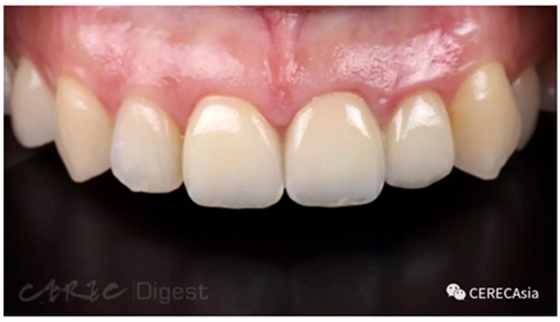

前來就診的 Sofia 是一名即將拍婚紗的年輕新婚女性,但原有的金屬燒附陶瓷(PFM)

牙橋的顏色及形狀不美觀,希望能尋求協(xié)助并重新制作。

許多病人的一開始的主訴都只針對(duì)舊的牙套,但經(jīng)過簡單的訪談,我發(fā)現(xiàn)她屬于高微笑線(high smile line) ,在說話或笑的時(shí)候都有過多的牙齦外露。

圖一、微笑照可以發(fā)現(xiàn)病人有 gummy smile 的情況,且 #21 #22 的牙齦有金屬透出的暗沉顏色。